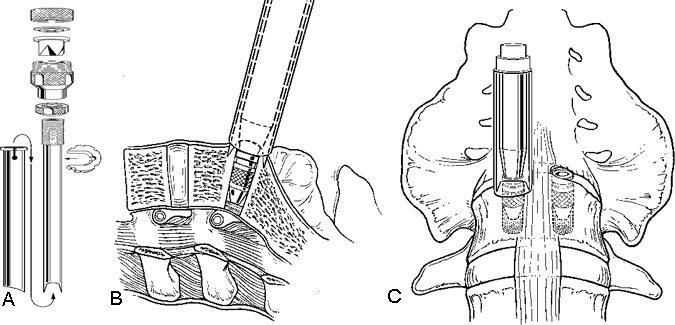

The suprapubic incision is lengthened to approximately 20 mm to fit the operating trochar for the hardware. The operating trochar is inserted over an introducing trochar. It is wide enough to fit the tools and cages.

The iliac vessels are gently retracted laterally with endoscopic vein retractors while the disc space is prepared and the hardware is inserted. The annulus of the disc space is marked using an alignment guide to identify the right and left entrance sites for the two threaded cages (Fig. 8). Holes are drilled at each entry site using an 8-mm diameter drill. The drill holes are oriented identical to the intended trajectory for the cages (Fig. 9). Disc material is removed from the drill holes with disc rongeurs (Fig. 10).

Distraction plugs are inserted sequentially into the holes in the disc spaces to reduce any spondylolisthesis, to distract the neural foramen, to apply tension to the annulus and ligaments, and to create space to fit the interbody fusion cages (Fig. 11). The distraction plugs should fit tightly into the disc space and should be difficult to remove. The diameter of the threaded interbody implant should be at least 3 mm wider than the diameter of the distraction plug so that it fits tightly.

After the disc space has been distracted, a drill tube trochar is inserted. The trochar has a valve mechanism to preserve the pressurized CO2 insufflation. The drill tube has a protective outer sheath. The inner sheath has retractable teeth to anchor the drill tube to the disc space (Fig. 12). After the drill tube guide is inserted, one distraction plug is removed and the pilot hole for the cage is reamed with a drill (Fig. 13). The pilot hole is tapped to cut the thread profile into the bone (Fig. 14).